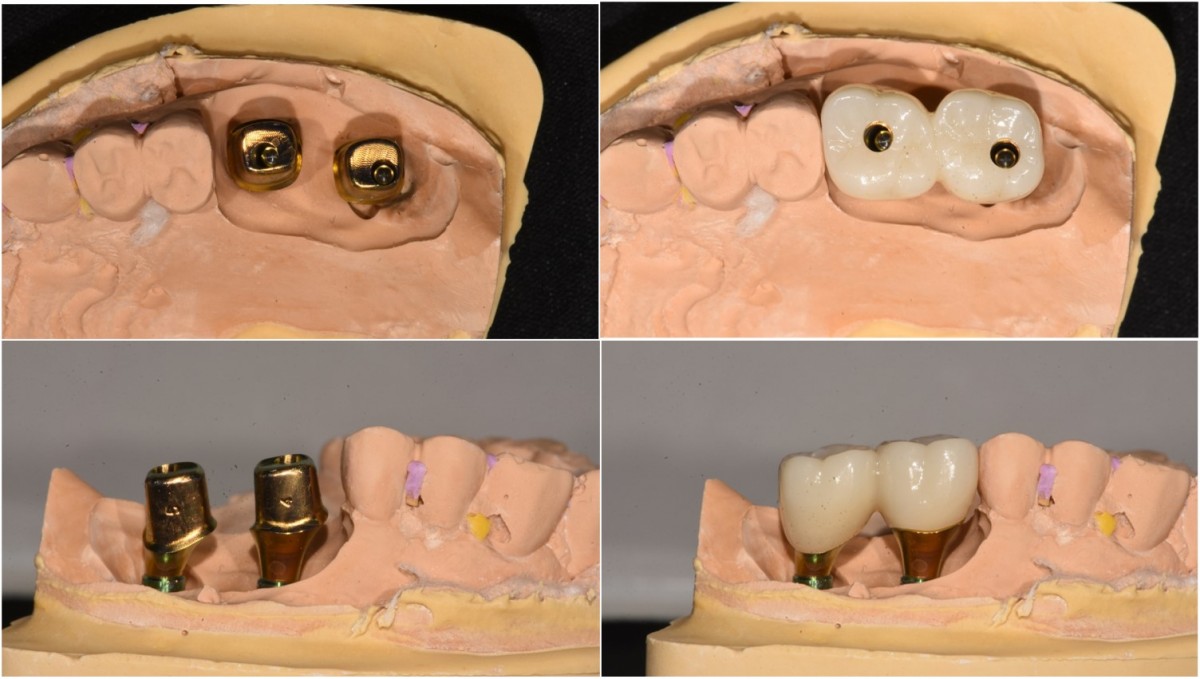

A 57-year-old male patient recently underwent

implant restoration on the maxillary right molar. This time, he is scheduled to

proceed with the left molars. (ARUM implant system)

▲2 implants were placed. ArumDentistry NB1 5*10 (30Ncm) in the 1st molar and 5*10 (10Ncm) in the 2nd molar.